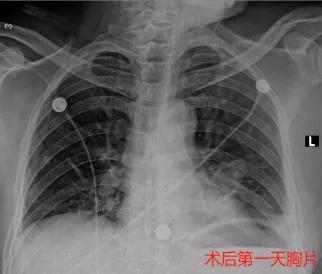

高德军副主任医师、马俊杰主治医师和臧一兵主治医师凭着胸腔镜手术的学习经验,严谨仔细,在麻醉科宋杰副主任、手术室护士邢小明、梁保栋的共同努力下,最终成功地完成胸腔镜下左肺下叶前外基底段切除+淋巴结清扫术。

术后患者恢复顺利,术后病理为微浸润腺癌,于8月30日出院。得到同事及家属的一致认可。